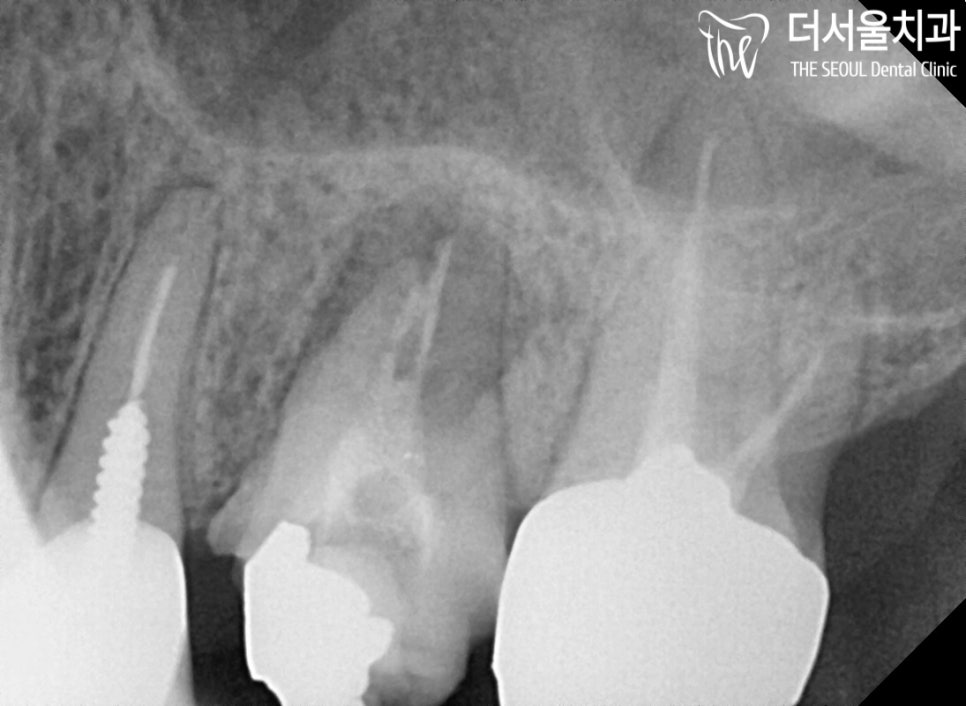

청소가 깔끔하게 되었는지

CT 촬영을 통하여 좀 더 정확히 살펴봅니다.

‘에이 그렇게 할 필요 있나요?’

‘그래요 혹시 뭐 조그맣게 남아있는게

문제를 일으킬 힘이 있을까요?’

네, 충분히 가능합니다.

그래서 다시 진료를 하게 되더라도

질병이 발생할 수 있으므로

처음에 확실히 처리하는게 좋습니다.